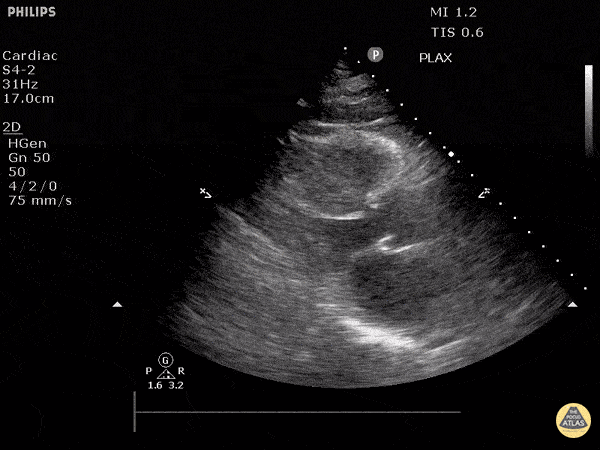

https://www.thepocusatlas.com/left-ventricular-dysfunction

View: Unspecified Parasternal Long Axis Parasternal Short Axis Apical Four-Chamber Subcostal Four-Chamber Subcostal Inferior Vena Cava Right Upper Quadrant Left Upper Quadrant Suprapubic Longitudinal Suprapubic Transverse Subxiphoid Anterior Thoracic Phrenic